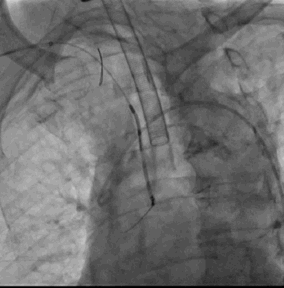

7. 退出LAmbre左心耳封堵器系统,术程顺利,右股静脉穿刺部位予缝线缝合,右桡动脉TR BAND加压包扎,左股动予Pro-Guide内缝包扎

Sentinel CPS系统在另一患者中應用捕抓到的左心耳血栓